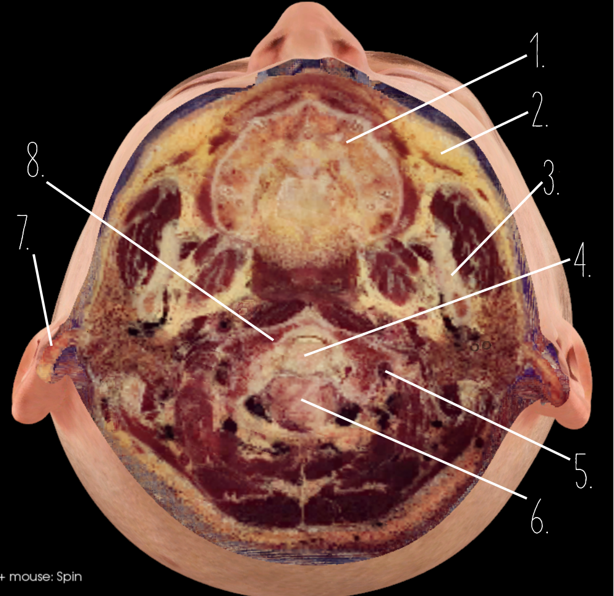

1?

Nasal Bone

2?

Maxillary Sinus

3?

External Acoustic Meatus

4?

Pons

5?

Cerebellum

6?

Mastoid Air Cells

7?

Mandibular Condyles

8?

Sphenoid Bone

9?

Maxillary Bone